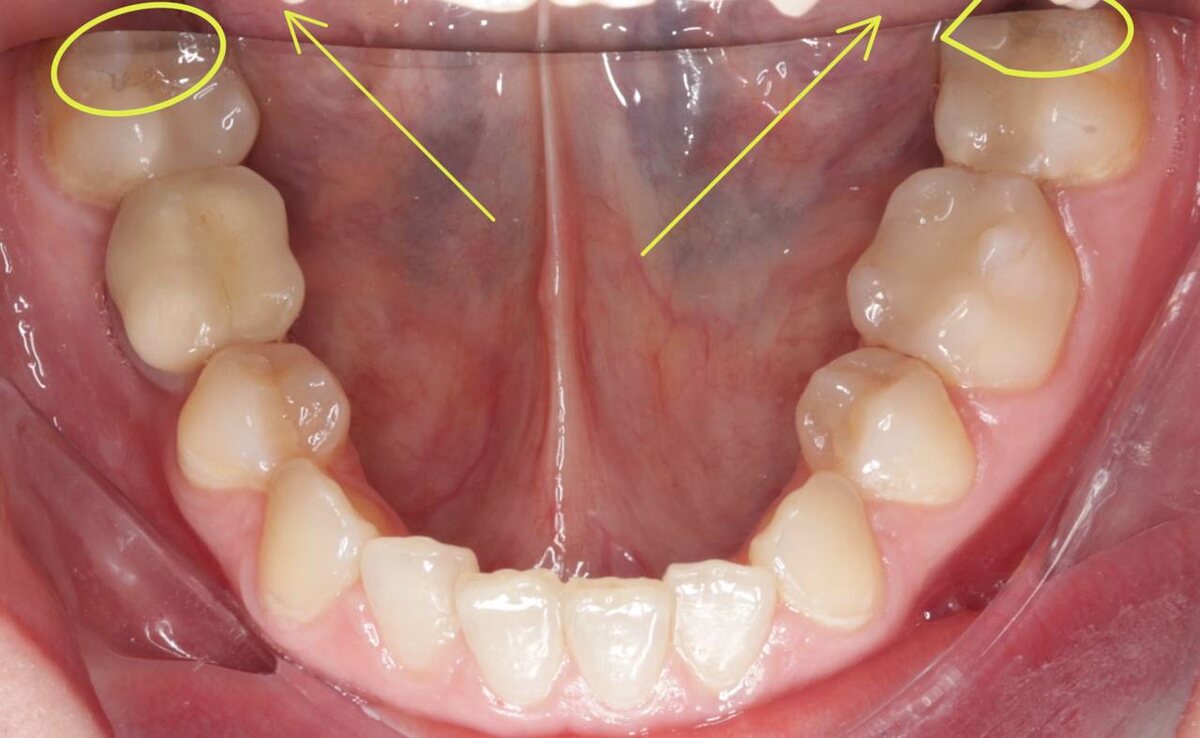

Нужно удалять 8ки? При условии всех Зубов кроме 8к на верхней челюсти

Нужно удалять 8ки? При условии всех Зубов кроме 8к на верхней челюсти?